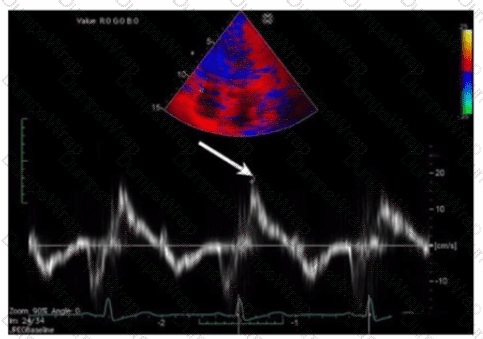

Which measurement is indicated by the arrow on this image?

AExplanation:

The Doppler tissue imaging waveform shown indicates the systolic annular velocity of the tricuspid valve annulus, labeled as S’. This measurement reflects right ventricular systolic function by quantifying the velocity of longitudinal myocardial motion during systole.

The a’ wave corresponds to atrial contraction, not systole. S’ assesses systolic function, whereas e’ and a’ relate to diastolic phases.

This assessment method is detailed in the "Textbook of Clinical Echocardiography, 6e", Chapter on Right Ventricular Function and Tissue Doppler Imaging【20:320-325†Textbook of Clinical Echocardiography】.